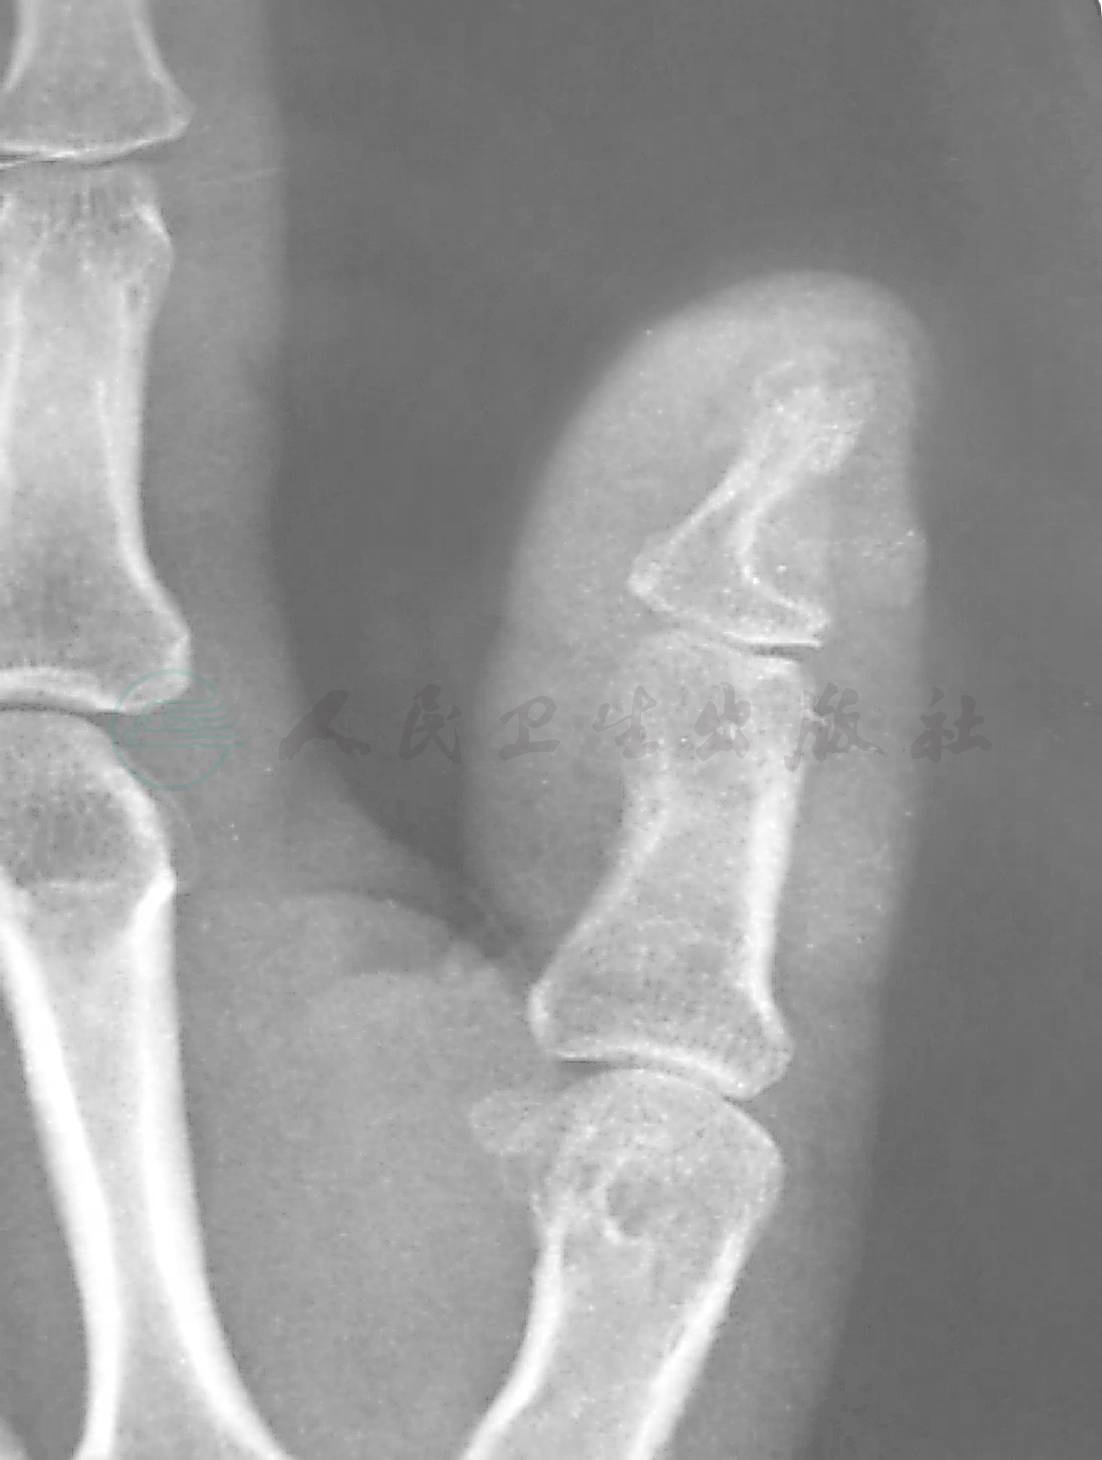

X线片上有时可见到指骨上有肿瘤的压迹。(图2)。

图2 左手拇指甲下血管球瘤,指骨上可见肿瘤压迹